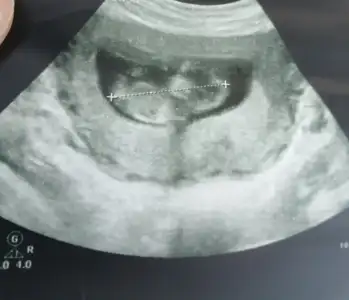

• 20ABBA81-603F-4423-BCBD-0A1C998B04DA.webp

20ABBA81-603F-4423-BCBD-0A1C998B04DA.webp

21,6 KB · Görüntüleme: 100

Merhaba canım doktor kordon mu erkek mi karar veremedi 2 hafta sonra bi daha gel dedi başta erkek diyecektim sonra kordon olduğunu anladım dedi kesin bişey diyemiyorum dedi sen bi bakabilir misin 🥺🙏🏻🙏🏻♥️♥️♥️ Ikra meyra Ikra meyra Ikra meyra Ikra meyra